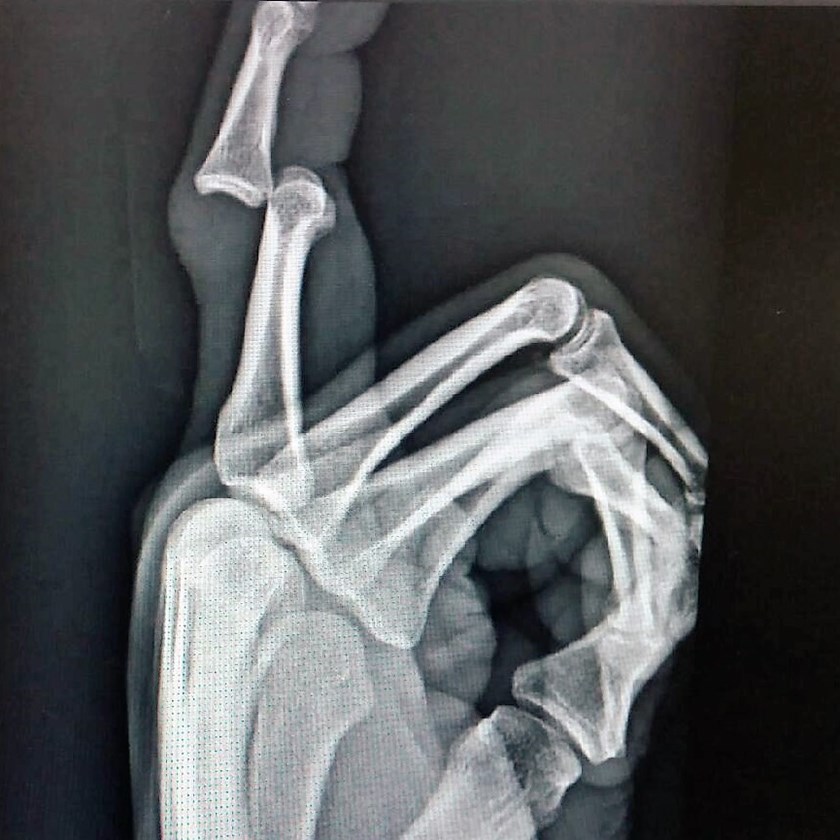

X-ray of Trent Merrin's injured right finger

Trent Merrin has undergone surgery on a fractured finger in Penrith's Nepean Hospital on Sunday as the Panthers' injury woes deepen following their 26-20 loss to the Cowboys.

Merrin's freak finger fracture in the warm-up, when he clashed with Sione Katoa in a contact drill, capped off a horror nine weeks for the Panthers, whose casualty ward includes Nathan Cleary, Waqa Blake, Dylan Edwards and Josh Mansour.